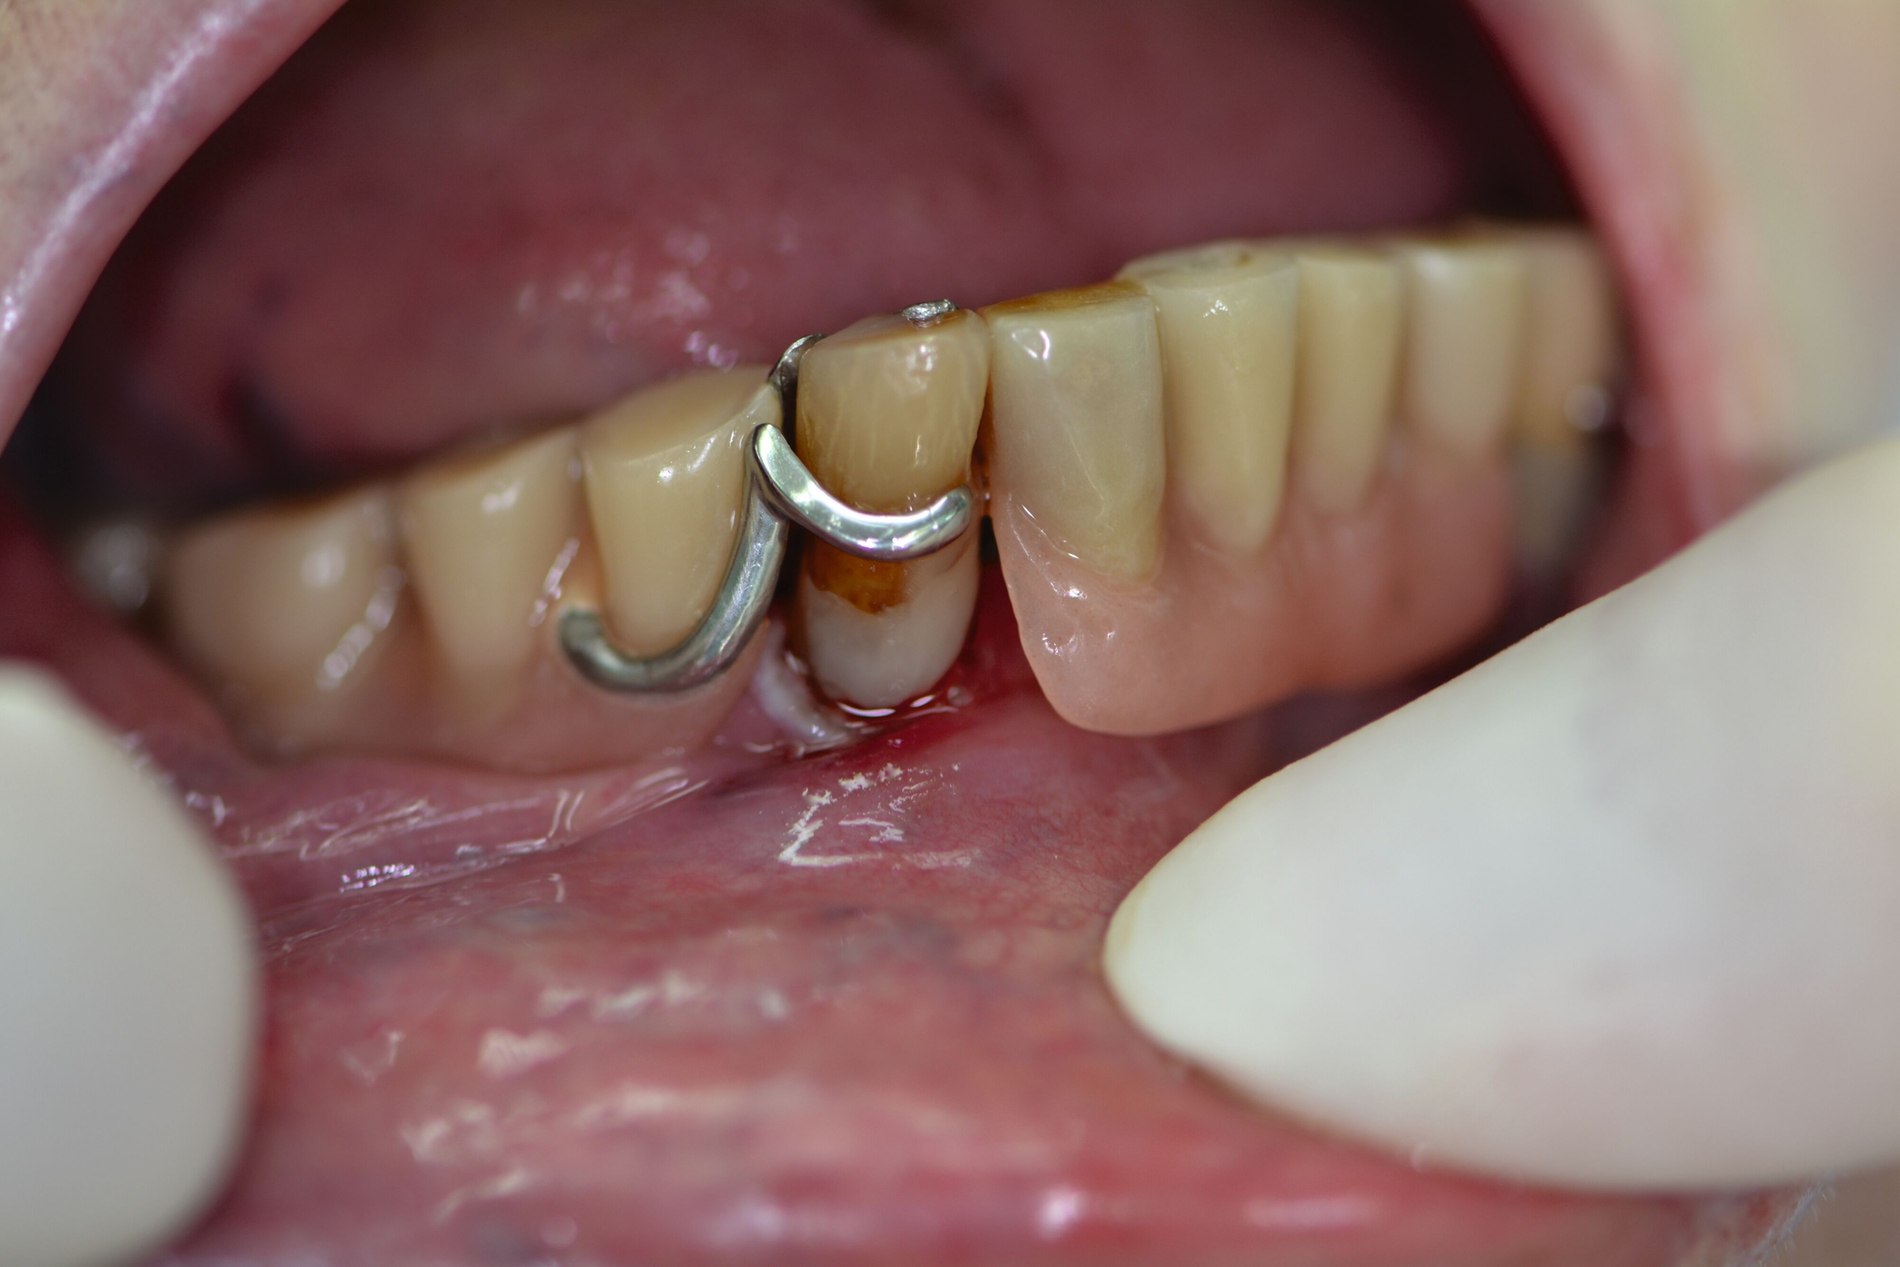

Auch aufseiten der Pflege wurden durch die Einführung des DNQP-Expertenstandards Rahmenbedingungen zur Verbesserung der Mundgesundheit bei Personen mit Pflegebedarf geschaffen. Der Expertenstandard definiert unter anderem das Aufgabenspektrum, den Verantwortungsbereich und das nötige Kompetenzprofil von Pflegefachpersonen in Bezug auf die Mundgesundheit bei Personen mit Pflegebedarf. Als zentrale Anforderung an Pflegefachpersonen formuliert der Expertenstandard zudem die Kompetenz, einschätzen zu können, wann weitere zahnmedizinische Expertise hinzuzuziehen ist [Sirsch et al., 2022]. Um die Maßnahmen zur Förderung der Mundgesundheit nachhaltig zu implementieren, ist ein dauerhafter Austausch zwischen Zahnmedizinern und Pflegeverantwortlichen, unter regelmäßiger Einbeziehung geriatrisch-hausärztlicher Expertise notwendig. Die Telemedizin verspricht in Bezug auf die Verbesserung des Zugangs zu zahnmedizinischen Leistungen für Personen in Pflegeeinrichtungen Zukunftspotenzial [Aquilanti et al., 2020]. Nicht in allen Fällen sind Defizite der Mundhygienefähigkeit absehbar. Nach Unfällen oder Schlaganfällen sind Patientinnen und Patienten eventuell von einem auf den anderen Tag nicht mehr in der Lage, ihre Mundhygiene selbstständig adäquat durchzuführen (Abbildung 4).

Patientinnen und Patienten mit stark reduzierter Therapiefähigkeit profitieren in besonderem Maß von zeiteffektiven Methoden und Materialien, zum Beispiel Bulk-fill-Kompositen, Reparaturfüllungen, Glasionomerzementen oder Intraoralscans. Die Therapiefähigkeit kann – ähnlich wie in der Kinderzahnmedizin – durch ein vertrauensvolles Verhältnis optimiert werden. Anders als in der Kinderzahnmedizin gibt es in der Alterszahnmedizin aber keine altersassoziierten Kontraindikationen für zahnmedizinische Interventionen. Voraussagbare Therapieergebnisse sind von besonderer Bedeutung, um erneute Behandlungen zu vermeiden. Das gesamte Spektrum zahnmedizinischer Interventionen kann bei der Behandlung von Personen mit Pflegebedarf sinnvoll sein. Die Abbildungen 6 bis 9 zeigen zahnmedizinische Interventionen bei Personen mit ausgeprägter Frailty (Stufe 7 der klinischen Frailty-Skala).